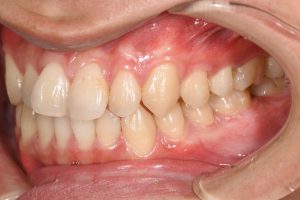

銀歯を全てセラミックにした症例

治療前

治療後

この患者様の場合

1回目にカウンセリング

2回目に型取り

3回目にセラミックのセット

の合計3回で治療終了となりました。